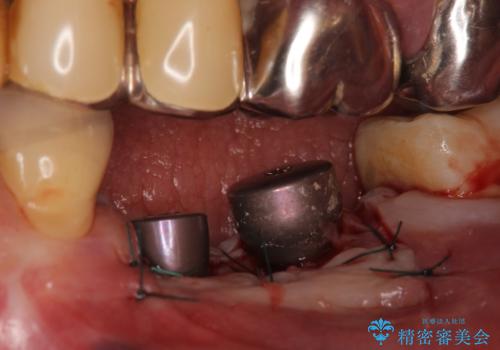

欠損部位である左下5、6番目にインプラントを埋入し、オールセラミッククラウンによる補綴を行いました。

カスタムアバットメントについて

カスタムアバットメントは患者様それぞれの歯茎に合わせて製作されたオーダーメイドのアバットメントです。

既製のアバットメントに比べ適合がよく、高い清掃性を誇ります。